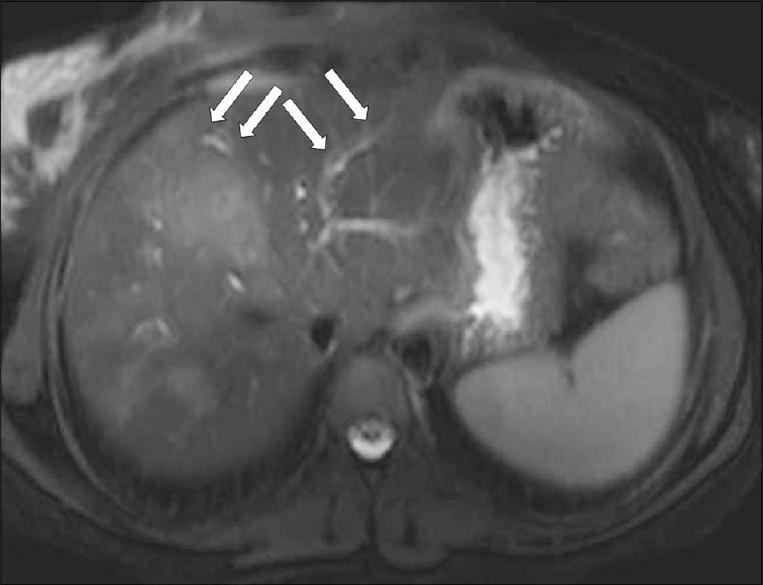

Fascioliasis refers to a zoonosis caused by Fasciola hepatica, a trematode infecting herbivores, but also occurs in humans who ingest the metacercaria found in fresh water plants. Infection in humans is common in developing countries and is also not uncommon in Europe. Diagnosis of this infection is difficult, as the history and symptoms are nonspecific and stool analysis for eggs is negative until the disease is in an advanced state by when the parasite has reached the biliary system. The clinical course consists of two phases; first a hepatic parenchymal phase in which immature larvae invade the liver parenchyma, followed by a ductal phase characterized by the excretion of larvae into the bile ducts. Parenchymal Phase: Ultrasonography (US) findings are nonspecific in this early phase. Computerized tomography (CT) may demonstrate subcapsular low attenuation regions in the liver. Magnetic Resonance imaging (MRI) can also be utilized to establish liver parenchymal involvement, and is better than CT in characterizing hemorrhagic lesions, as well as identifying more lesions relative to CT. Ductal Phase: US examination is most useful at this stage, with its ability to demonstrate the live movement of the worms within the dilated ducts. A CT demonstrates dilated central biliary ducts with periportal tracking, whereas, mild ductal dilatation is poorly appreciated under MRI. Therefore, familiarity with the multimodality imaging features of fascioliasis, in combination with an available confirmatory enzyme-linked immunoassay, would be most helpful for early diagnosis.

肝片吸虫病是一种由肝片吸虫引起的人畜共患病,这种吸虫感染食草动物,但人类摄入淡水植物中的囊蚴后也会感染。在发展中国家,人类感染这种疾病很常见,在欧洲也并不罕见。这种感染的诊断很困难,因为病史和症状不具有特异性,而且在疾病发展到晚期寄生虫进入胆道系统之前,粪便虫卵分析一直呈阴性。临床病程包括两个阶段:首先是肝实质期,未成熟幼虫侵入肝实质,随后是导管期,其特征是幼虫排入胆管。实质期:在此早期阶段,超声检查(US)结果不具有特异性。计算机断层扫描(CT)可能显示肝脏包膜下低密度区域。磁共振成像(MRI)也可用于确定肝实质受累情况,在表征出血性病变以及相对于CT识别更多病变方面比CT更好。导管期:US检查在这个阶段最有用,它能够显示扩张胆管内虫体的活动。CT显示中央胆管扩张并伴有门静脉周围条索状影,而在MRI下轻度胆管扩张不易被察觉。因此,熟悉肝片吸虫病的多模态影像学特征,并结合可用的确诊酶联免疫测定,对早期诊断最有帮助。